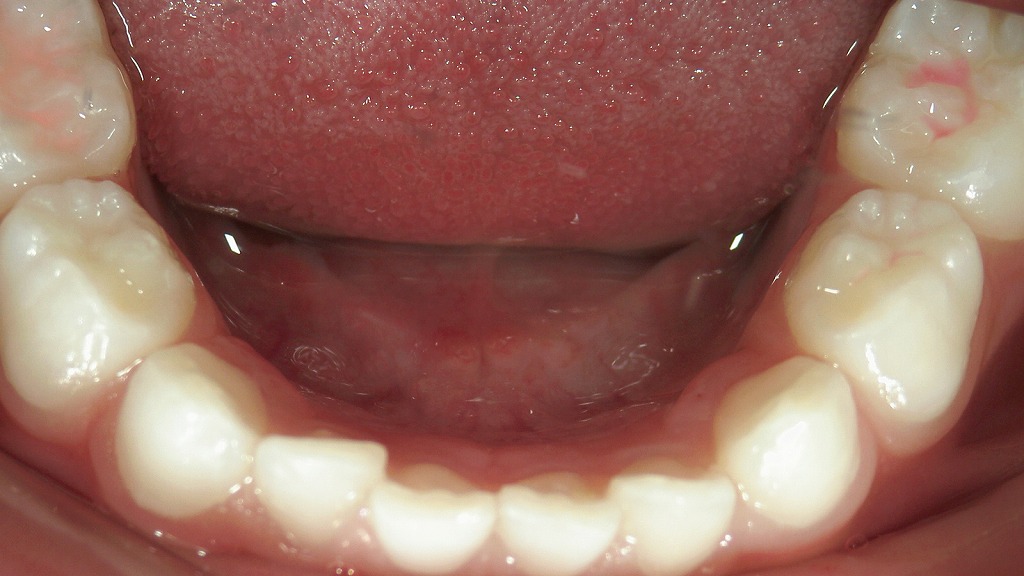

📷霊長空隙が存在する症例

乳歯の歯と歯の間にほとんど隙間がなく、全体的にキュッと詰まっている状態が確認できます。

本来、乳歯の時期は永久歯が大きくなるスペースを確保するために、**歯と歯の間に自然なすき間(霊長空隙・発育空隙)があるのが理想です。

この症例のように隙間がない場合、永久歯が生えてくる際に歯並びがガタつきやすい(叢生になりやすい)**傾向があります。